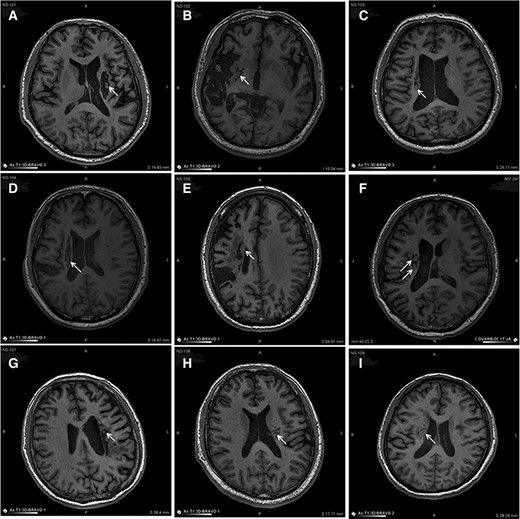

圖中顯示的是所有9名受試者(#101–109)在NSI-566移植后最新隨訪時的T1MRI圖像。箭頭指示梗塞腔位置。

(A):#101,24個月時,(B)#102,12個月時,(C)#103,14個月時,(D) #104,9個月時,(E)#105,14個月時,(F)#106,24個月時,(G) #107,21個月時,(H) #108,12個月時,(I) #109,14個月時。所有九個病例中梗塞腔內(nèi)均有新組織生長。